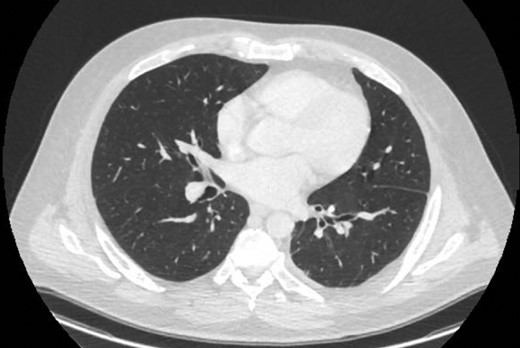

Chest X-ray in ICU following drainage showed what was thought to be Pneumomediastinum (Figs 1 and 2), and given this concern he was referred to the Cardiothoracic service. Subsequent CT suggested a large loculated hydro-pneumothorax, which in retrospect represented the drained Pseudocyst communicating through the diaphragm (Figs 3 and 4).

Sagittal view CT Chest revealing large residual space with loss of left lung volume due to the pseudocyst. Image post-transgastric drainage.

Area of communication between the drained Pseudocyst and the Left Pleura. Space noted with arrow.